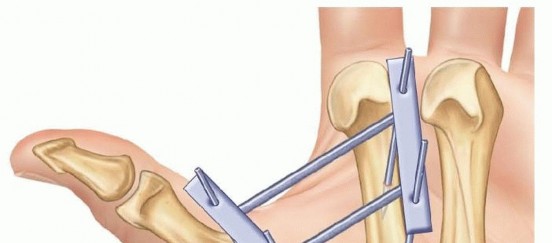

Closed Reduction and Percutaneous Pinning (CRPP)

CRPP is the treatment of choice for classic Bennett fractures where the volar-ulnar fragment is too small to reliably accept a lag screw, yet the joint can be anatomically reduced closed. The reduction maneuver is highly specific, designed to counteract the deforming forces of the APL and Adductor Pollicis. Longitudinal traction is applied to the thumb, followed by palmar abduction and pronation. Direct pressure is then applied to the dorsal-radial aspect of the metacarpal base, effectively pushing the shaft back into the anatomic cradle of the intact volar-ulnar fragment.

Once anatomic reduction is confirmed via multi-planar fluoroscopy, percutaneous fixation is achieved. Typically, two 0.045-inch or 0.062-inch Kirschner wires are utilized. The first wire is driven from the dorsal-radial aspect of the metacarpal shaft directly into the trapezium, effectively neutralizing the proximal pull of the APL. A second wire is often placed transversely from the first metacarpal shaft into the second metacarpal to control rotation and maintain the web space. Pins are cut outside the skin and capped to facilitate easy removal in the clinic.